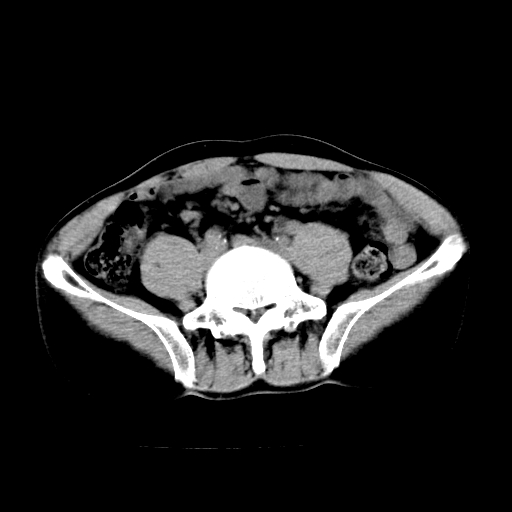

男,47岁,左输尿管结石碎石治疗后10余日。彩超示:左输尿管下段狭窄、输尿管积水。请各位讨论一下左输尿管下段结石还是静脉石?

象是第二狭窄处结石伴以上输尿管、肾盂轻度积水。

输尿管结石伴以上输尿管、肾盂轻度积水。

两侧髂总动脉壁斑状及点状钙化.左侧输尿管行经与左髂总动脉相交后见高密度影,且下段输尿管管腔未见扩张,应该要考虑结石伴以上输尿管及肾盂积水.但右侧结节状高密度影,也应该是结石吧!那以上输尿管未见扩张呢!因此静脉结石可能性也较大.请问楼主碎石前左侧输尿管结石位置.

虽左侧有轻度肾盂积水但不支持结石。1结石边周应该有软组织包绕呈晕征。2钙化点前面见输尿管影也不支持是结石。3彩超没提结石。建议超生复查。

输尿管先位于腹部,后进入盆腔,最后斜穿膀胱壁开口于膀胱,因此,临床上常将输尿管分为腹段、盆段和壁内段。第1个狭窄:在肾盂与输尿管移行处。第2个狭窄:在跨过髂血管处。第3个狭窄:在穿过膀胱壁处。这些狭窄是结石容易滞留的部位。

左侧输尿管有轻度扩张伴有肾盂积水,输尿管下段周围的高密度影不象在输尿管内。

同意,不支持结石。(因显示该高密度影前见扩张输尿管影,另外两侧对称显示)。

左侧高密度影在左侧输尿管的内侧方,所以不考虑输尿管结石.

我认为不是结石的可能性大,因为他的位置和血管钙化的位置邻近